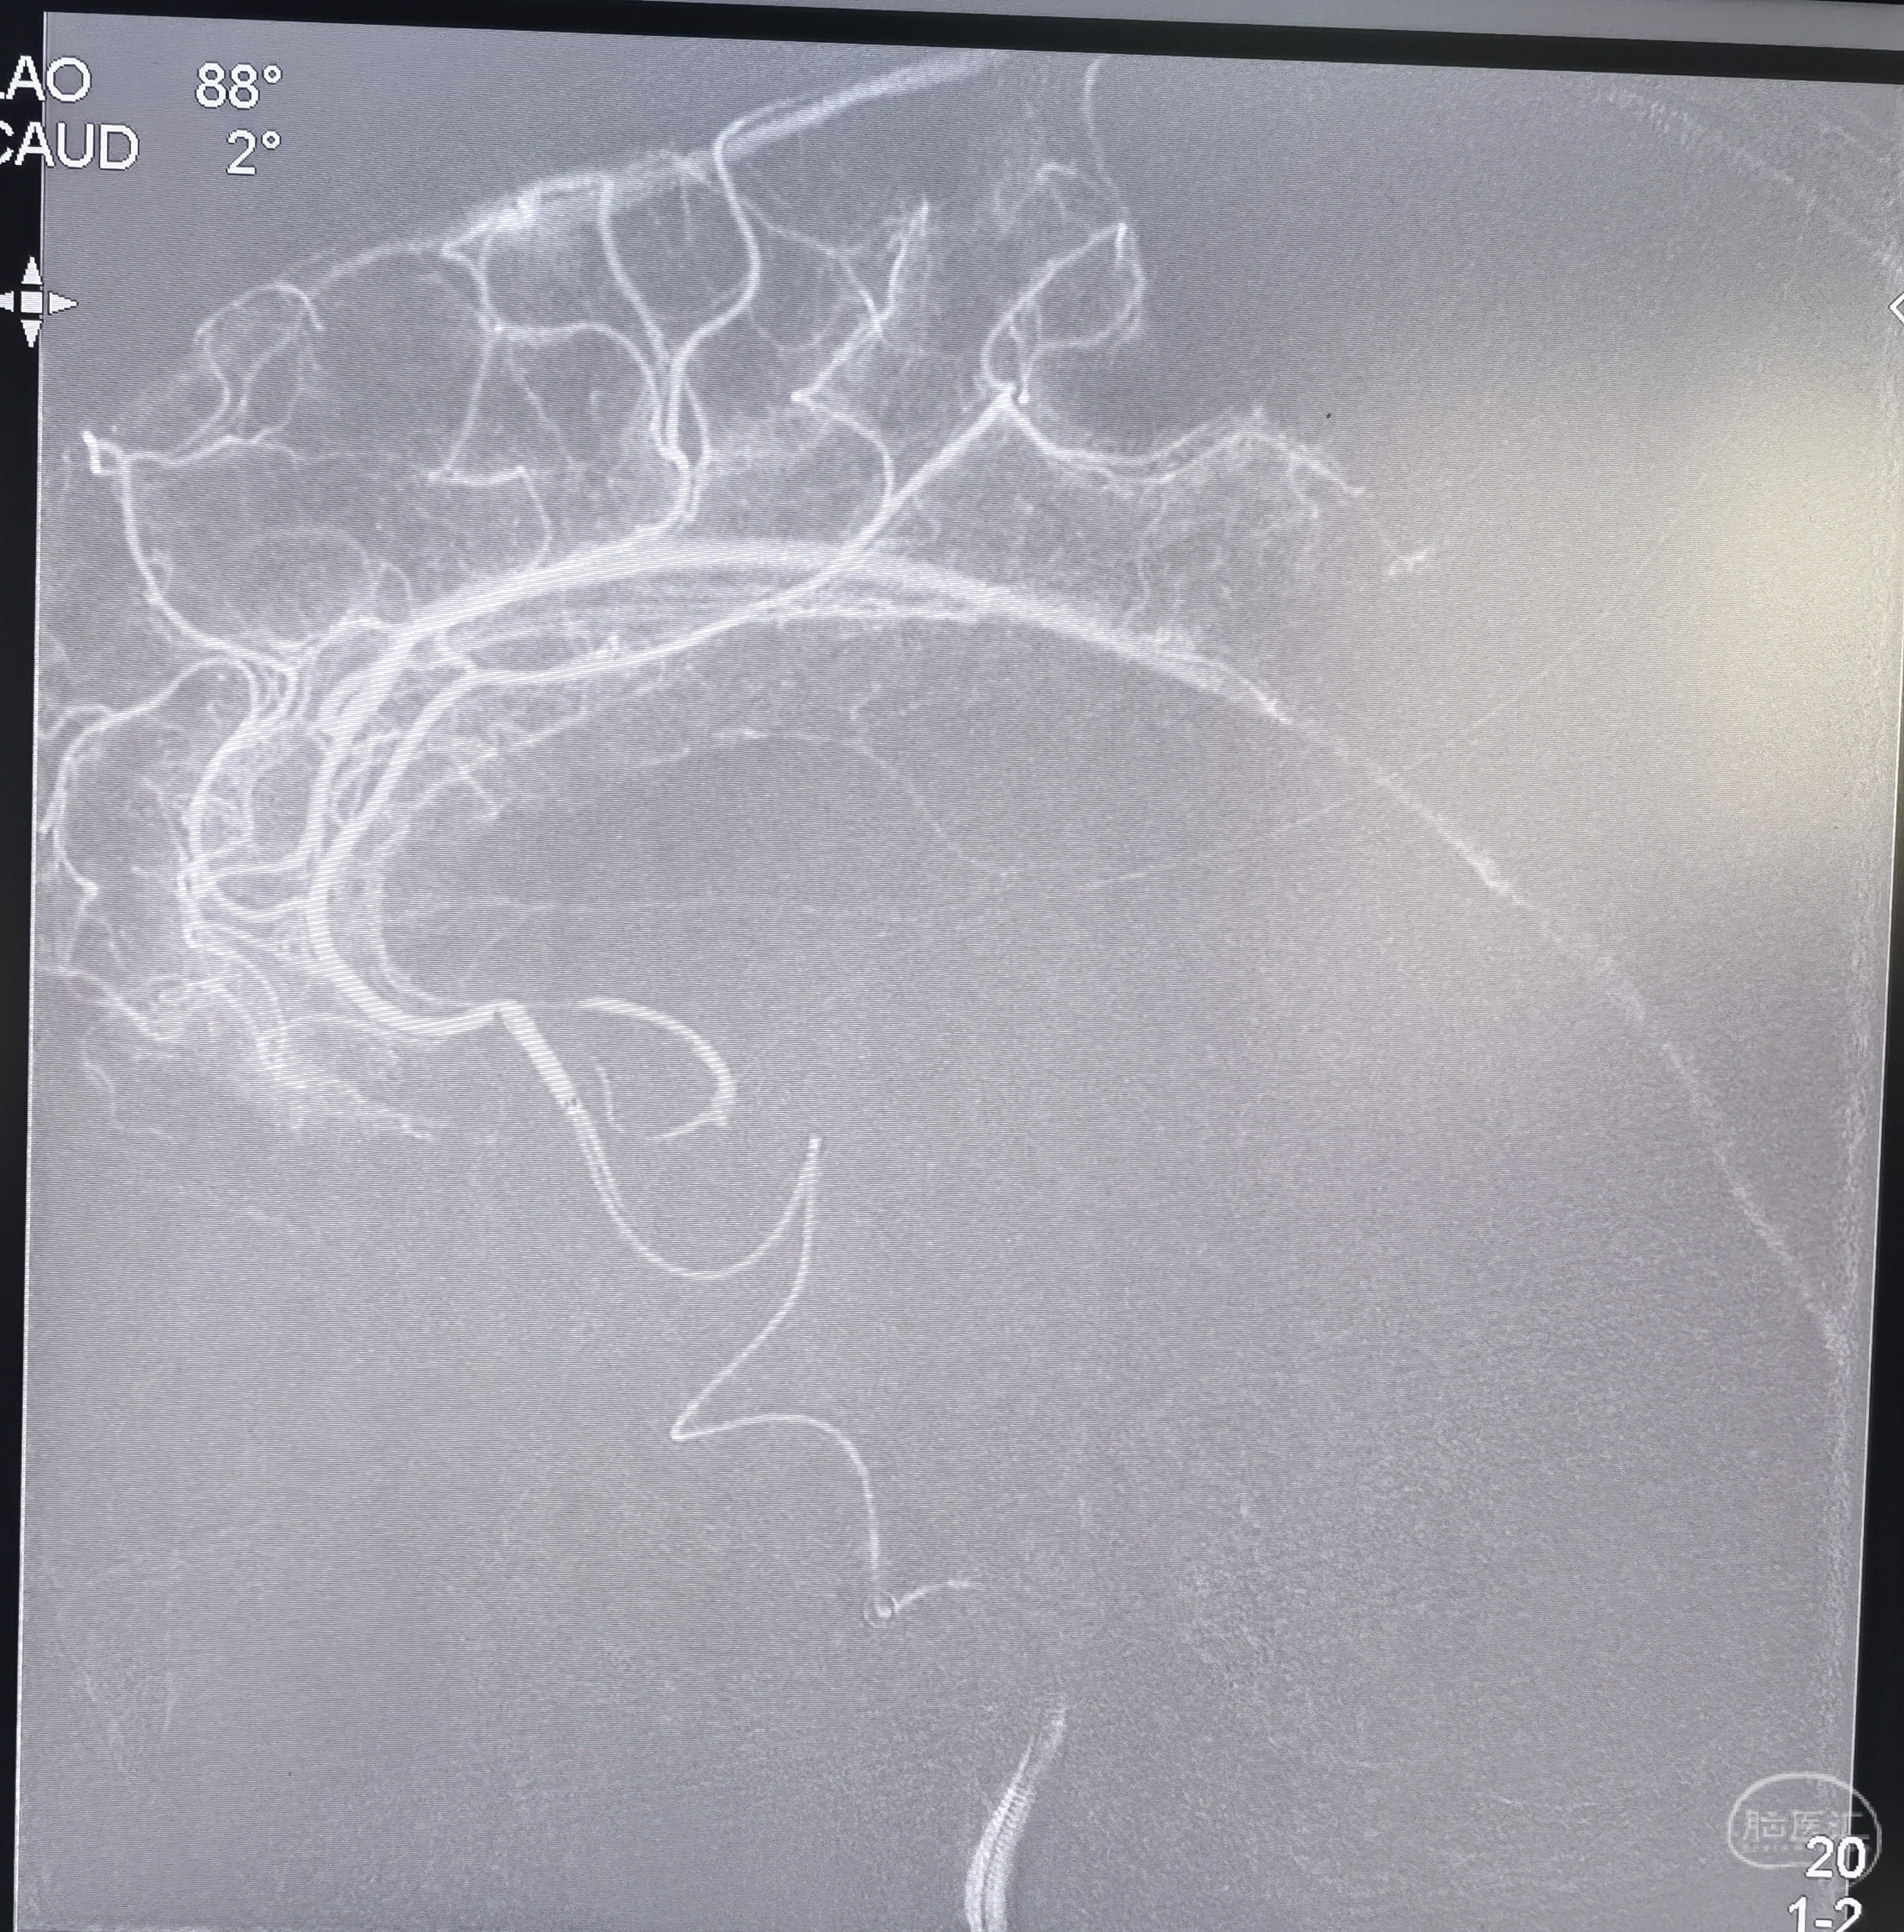

通过颈内动脉闭塞段后正位造影